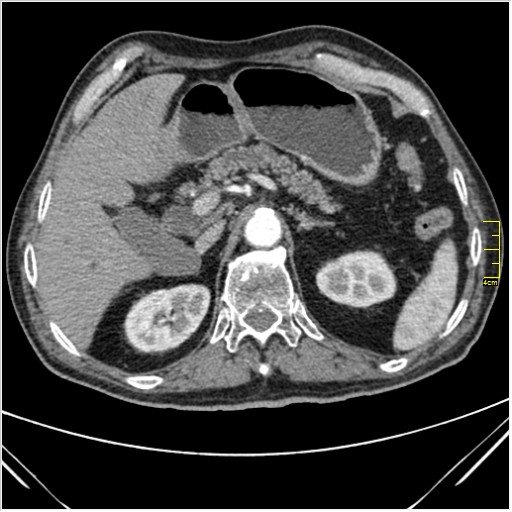

Мужчина 62 года с желтухой

Опухоль головки поджелудочной железы, расширение холедоха и панкреат. протока (Double Channel sign)

Карциномы панкреас гиподенсны на КТ с болюсом, т.к. содержать много соединительной и фиброзной ткани, в отличие от нормальной ткани железы, которая (как любая железа) хорошо васкуляризирована. Поэтому если видим в панкреас солидное гиподенсное образование - всегда настораживает на предмет рака. Второй момент: обязательная оценка взаимоотношения опухоли к ВБА и ВБВ, на предмет оценки операбельности.